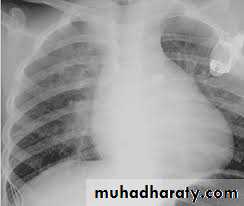

CXR:

Prominent

Pulm. AProminent

Pulm. marking

Cardiomegaly

• CXR show marked cardiomegaly and pulmonary edema.